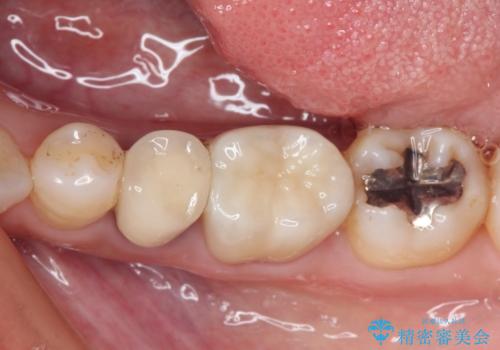

- 奥歯の銀歯をセラミックの白い歯にして、しみる症状も改善したいとのことで来院された患者様です。

知覚過敏の症状が強い歯と、銀歯の範囲や銀歯の下のむし歯が大きい歯は、インレー修復では対応が難しいためオールセラミッククラウンで、インレー修復で対応が可能な歯ではセラミックインレーにて修復することとしました。